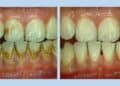

有牙周病的病人,常會因齒槽骨破壞,造成牙齒的動搖及位移,牙齒與牙齒之間不再緊密相鄰,反而出現了縫隙,這種情形在門牙特別明顯。常聽到病人說「以前牙齒很整齊,現在變長了」、「以前牙齒很整齊,現在這顆牙越來越突出來」,或是「以前牙齒很整齊,沒有牙縫,現在牙縫越來越大」。這些都可能是牙周病的症狀,因為它表現在前牙美觀區,所以人們會特別注意到,更會影響到別人對你的印象。

首先,我們要「治療牙周病」。包括第一階段基本治療,視需要再進行第二階段手術治療,之後需有2到3個月的癒合觀察期。經過治療後,牙周發炎狀況已控制穩定,在某些情況下有些牙齒可以自動恢復原位,無法復原的牙齒,則可利用「矯正」的方式讓它縫隙關閉並且排列整齊。